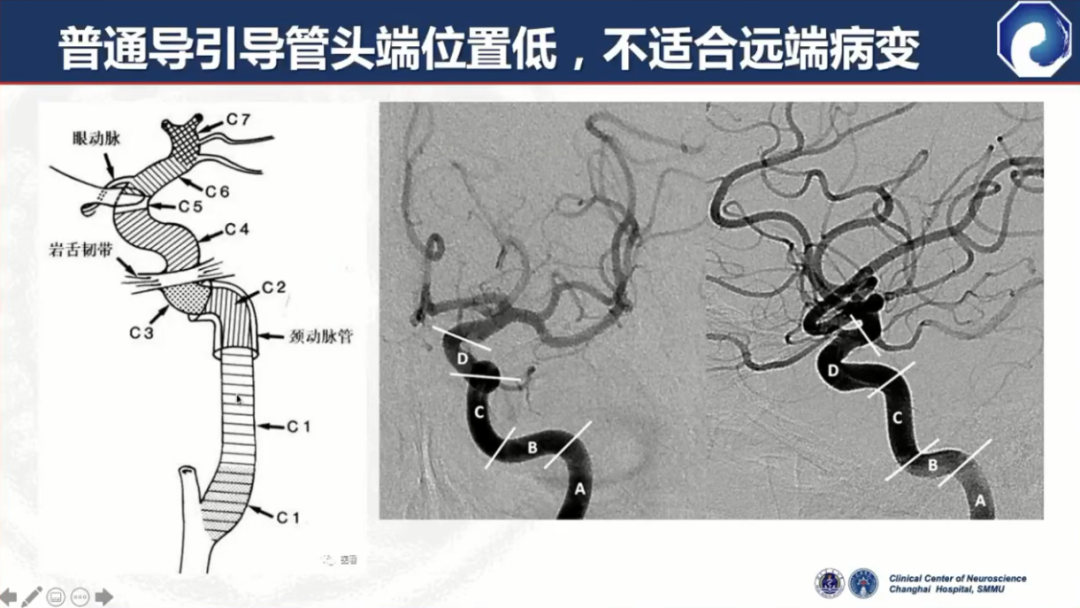

头端到位低,不适合远端病变

在迂曲血管中通过性能较差